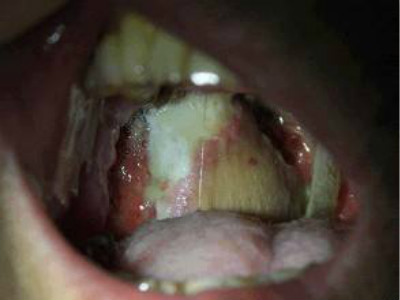

扁桃體惡性腫瘤圖片

扁桃體癌圖 (9)

扁桃體癌圖 (63)